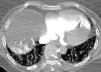

Contrast-enhanced multidetector CT showed “passive” filling of the right cardiac chambers with contrast material occupying the lower part of the chambers.

Retrograde flow of the contrast agent was also observed through the right atrium into the coronary sinus and the great cardiac vein, filling the cardiac veins of the left ventricle (Fig. 1), and from the inferior vena cava into the right hepatic vein and right hepatic lobe (Fig. 2).

These findings are pathognomonic of the absence of blood flow during the procedure.